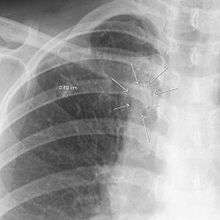

The arrows denote an ill-defined nodular opacity in medial aspect of right upper lobe with ill-defined rim of lucency surrounding it.